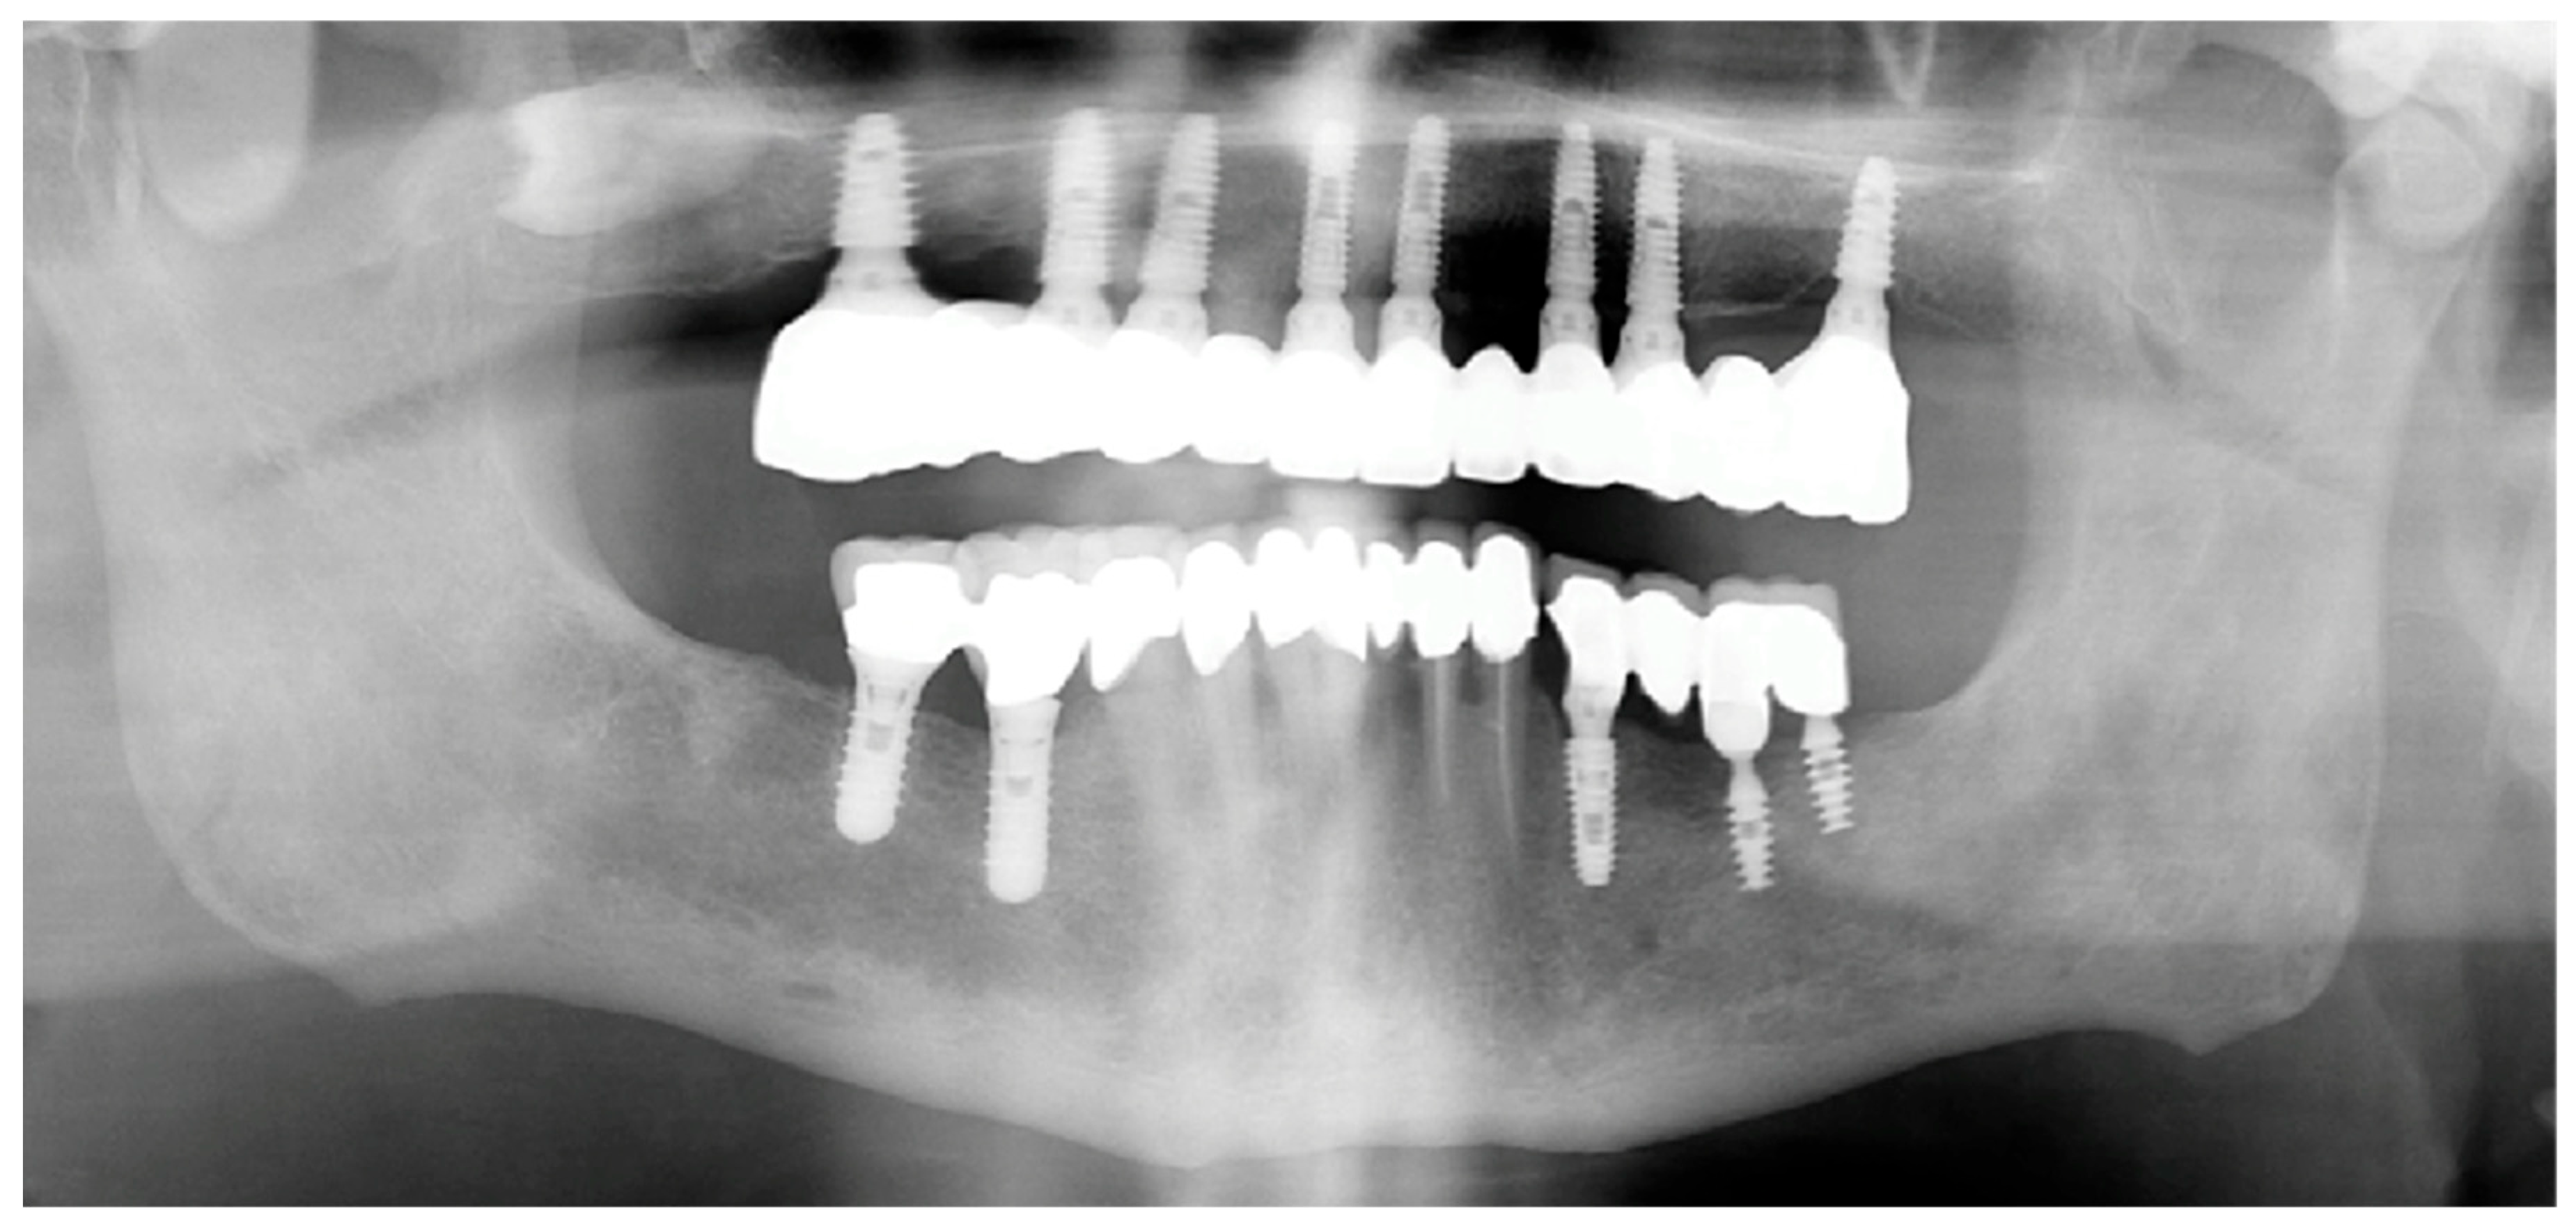

Patients were recalled every three months up to a 6-month follow-up period to evaluate the presence of biological or technical complications (Figure 5).

3.3. Secondary Outcomes: Implant and Prosthesis Survival

At the 6-month follow-up, no implant failures were recorded, resulting in an implant survival rate of 100%. Similarly, no prosthesis failures occurred, yielding a prosthesis survival rate of 100%. No biological complications, including peri-implant mucositis or peri-implantitis, were observed during the follow-up period. Likewise, no technical complications, such as screw loosening or framework fracture, were recorded in any of the treated cases. Data are summarized in Table 2.

Figure 5. Six-month orthopantomogram (OPT).